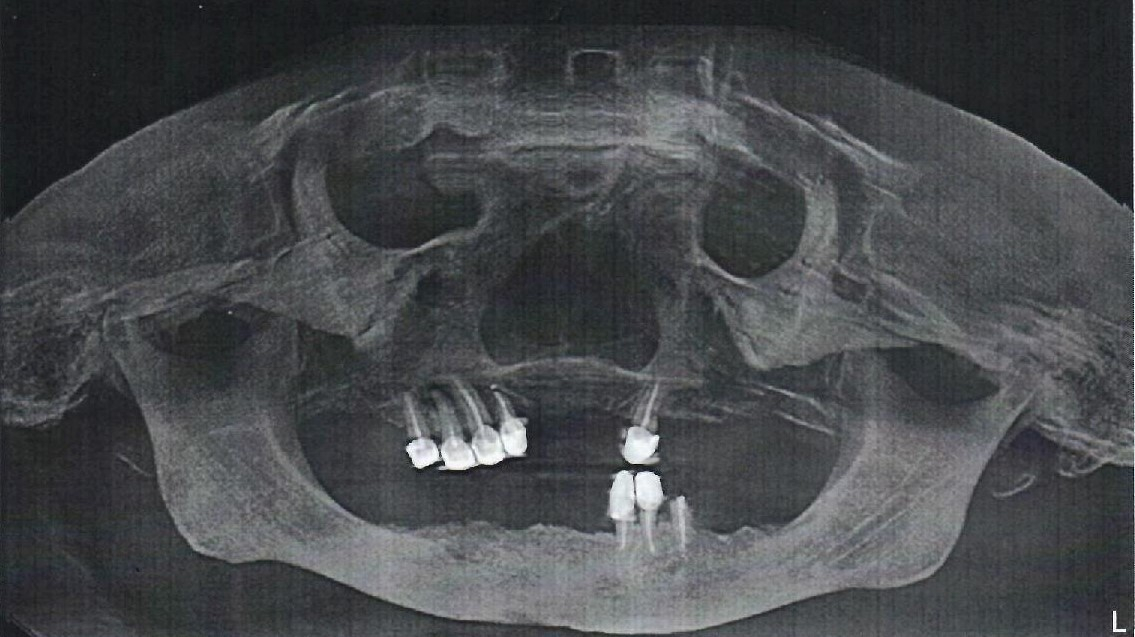

— Наши врачи постоянно сталкиваются со сложными ситуациями, которые требуют тщательного подхода к решению проблемы полости рта. На фото вы можете видеть примеры наших работ.